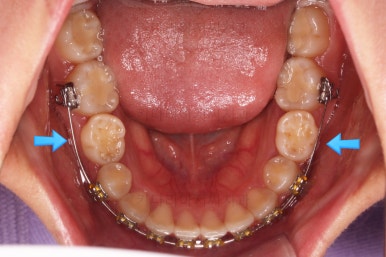

초진 때의 입안 모습입니다.

원래 다니던 치과에서 1년여 교정치료를 진행하신 상태였는데요.

몇 가지 이상한 점이 보이죠?

한 쪽만 발치가 되어있다.

아랫니에 유치가 2개가 그대로 남아있다.(화살표)

몇몇 이아에는 장치가 부착되어 있지 않다.